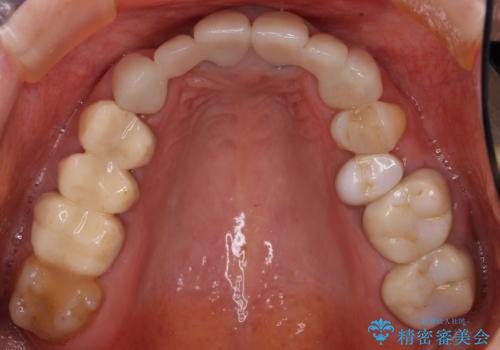

- 他院で仮歯まで入れたものの違和感があることを主訴に来院された患者様です。

違和感があると訴えたにも関わらずそのまま被せようとする他院に不安を感じ、通院をやめてしまったとのことでした。

丁寧にう蝕除去と再根管治療を行い症状の改善を確認したのち、セラミッククラウン及びセラミックインレーによる補綴を行いました。

- ¥550,000 (根管治療×1本、土台×1本、クラウン×3本、インレー×1本) ※税込費用は治療当時の料金となります